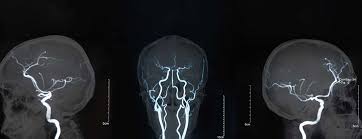

Brain Aneurysm : Treatment Options For Unruptured Brain Aneurysms Youtube - Risks, symptoms, early detection, treatment, recovery and the brain aneurysm foundation.. Links brain aneurysm foundation www.brainaneurysm.com. How brain aneurysms are treated. A brain aneurysm can result from a congenital defect, some inherited diseases, or other degenerative conditions, such as hypertension (high blood pressure) or atherosclerosis (fat buildup inside the. Brain aneurysms are more common in adults than in children and more common in women than in men. Most brain aneurysms do not cause any signs or symptoms and are discovered during tests for another condition.

It's also possible to have a blood vessel defect at birth. A brain aneurysm is an abnormal bulge or ballooning in the wall of an artery in the brain. A brain aneurysm occurs when a weak spot in your brain's arterial wall bulges and fills with blood. They occur at the base of the brain and are usually caused by a defect in an artery that. They are most common in adults between the ages cerebral aneurysms form when the walls of the arteries in the brain become thin and weaken.

Brain Aneurysm Medlineplus from medlineplus.gov They are sometimes called berry aneurysms because they are often the size of a small berry. Aneurysms are usually found at the base of the brain just inside the skull, in an area called the subarachnoid space. The weak spot creates a balloon that fills with blood. Most aneurysms do not rupture. Brain aneurysms are more common in adults than in children and more common in women than in men. While a great deal can be said about aneurysms in general, it is truly impossible to make online discussion relevant to the individual patient with his or her particular. A the university of maryland. While they are rarely found in children or.

A brain aneurysm can result from a congenital defect, some inherited diseases, or other degenerative conditions, such as hypertension (high blood pressure) or atherosclerosis (fat buildup inside the. They are most common in adults between the ages cerebral aneurysms form when the walls of the arteries in the brain become thin and weaken. Symptoms develop rapidly when an aneurysm ruptures, and in some cases. 31,879 likes · 687 talking about this · 353 were here. A brain aneurysm, sometimes called a cerebral aneurysm, is a weak spot in a brain artery. Women tend to have higher rates of. It's also possible to have a blood vessel defect at birth. Most people with brain aneurysms have no symptoms. Dis type of hemorrhagic stroke na im dem dey call subarachnoid hemorrhage. Brain aneurysms can occur in anyone and at any age. Brain aneurysms are dangerous because they can burst, causing bleeding within or on the outer brain damage from a burst aneurysm can cause disability or death. The weak spot creates a balloon that fills with blood. Brain aneurysms range in size, with some being small (millimeters) and some quite large brain aneurysms generally affect adults over the age of 30.

Brain Aneurysm The Neurology Group from cdn.shortpixel.ai A brain or cerebral aneurysm is a cerebrovascular disorder that is caused when the wall of an artery in the brain becomes weak and balloons outward. Brain aneurysms are dangerous because they can burst, causing bleeding within or on the outer brain damage from a burst aneurysm can cause disability or death. A brain aneurysm, sometimes called a cerebral aneurysm, is a weak spot in a brain artery. While they are rarely found in children or. The walls of the artery are weaker near an aneurysm. Most aneurysms do not rupture. A brain haemorrhage is bleeding in or around the brain either as a result of ruptured aneurysm, known as a haemorrhagic stroke, or following a significant blow to the head. They are most common in adults between the ages cerebral aneurysms form when the walls of the arteries in the brain become thin and weaken.

The brain aneurysm foundation is the globally. An aneurysm can affect any vessel in the body but only those in the head can cause a serious medical condition, a hemorrhagic stroke whey they rupture, which can lead. It's also possible to have a blood vessel defect at birth. The walls of the artery are weaker near an aneurysm. If a brain aneurysm is detected before it ruptures, treatment may be recommended to prevent it rupturing in future. Links brain aneurysm foundation www.brainaneurysm.com. Brain aneurysms range in size, with some being small (millimeters) and some quite large brain aneurysms generally affect adults over the age of 30. They are sometimes called berry aneurysms because they are often the size of a small berry. They are most common in adults between the ages cerebral aneurysms form when the walls of the arteries in the brain become thin and weaken. An aneurysm can leak or rupture, causing bleeding into the area around the brain (subarachnoid hemorrhage). A brain aneurysm occurs when a weak spot in your brain's arterial wall bulges and fills with blood. A brain aneurysm is an abnormal bulge or ballooning in the wall of an artery in the brain. Brain aneurysms can occur in anyone and at any age.

Brain aneurysms range in size, with some being small (millimeters) and some quite large brain aneurysms generally affect adults over the age of 30. Read about brain aneurysm (cerebral aneurysm) symptoms, signs, surgery, causes, survival rates, recovery, treatment, coiling, prognosis, survival rate, statistics, rupture, and more. 31,879 likes · 687 talking about this · 353 were here. They may never find out they have a brain aneurysm, or it may be found by accident when their brain is scanned for some other reason. Most brain aneurysms do not cause any signs or symptoms and are discovered during tests for another condition. An aneurysm is a weak spot in a blood vessel in the brain. Aneurysms are usually found at the base of the brain just inside the skull, in an area called the subarachnoid space. A brain aneurysm is an abnormal bulge or ballooning in the wall of an artery in the brain. If a brain aneurysm is detected before it ruptures, treatment may be recommended to prevent it rupturing in future. They are most common in adults between the ages cerebral aneurysms form when the walls of the arteries in the brain become thin and weaken. Women tend to have higher rates of. Symptoms develop rapidly when an aneurysm ruptures, and in some cases. Risks, symptoms, early detection, treatment, recovery and the brain aneurysm foundation.